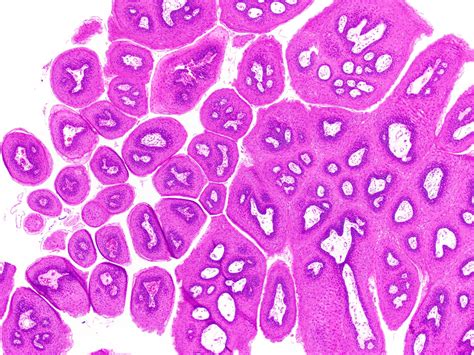

Identifying an Oral Squamous Papilloma often involves observing its distinct morphology. Clinicians look for specific visual cues that differentiate this lesion from other oral pathologies like focal epithelial hyperplasia or squamous cell carcinoma. Because they are exophytic, they grow outward from the surface, often resembling a small cluster of grapes or a delicate cauliflower head.

• Biopsy: The gold standard for diagnosis. A small sample of the tissue is removed and examined under a microscope to confirm the presence of koilocytes—cells characteristic of HPV infection.